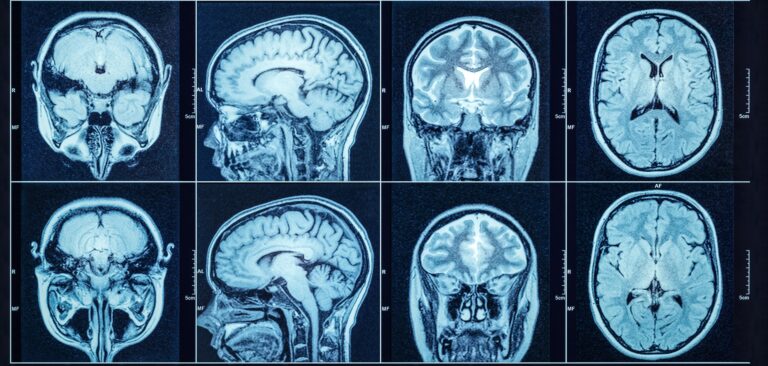

Brain Cancer Awareness is about more than a diagnosis—it’s about education, early detection, and support for those impacted. Although brain cancer is relatively rare, it can be life-altering. Raising awareness helps ensure symptoms aren’t ignored and encourages people to seek timely care.

Because the brain controls so many vital functions, even small tumors can have serious effects. Some brain tumors are benign (non-cancerous), while others are malignant and may grow rapidly. In either case, early diagnosis leads to more treatment options and better outcomes.

During Brain Cancer Awareness Month, we’re committed to spreading knowledge, offering support, and encouraging regular check-ups when symptoms appear.